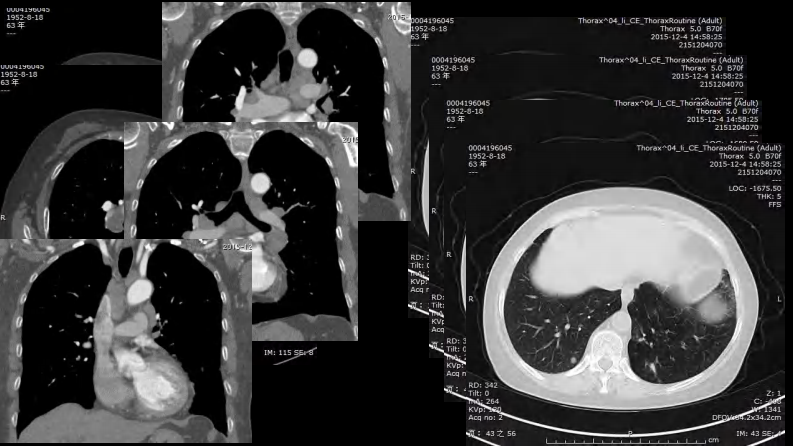

胸部结节病综合影像学交流.pdf